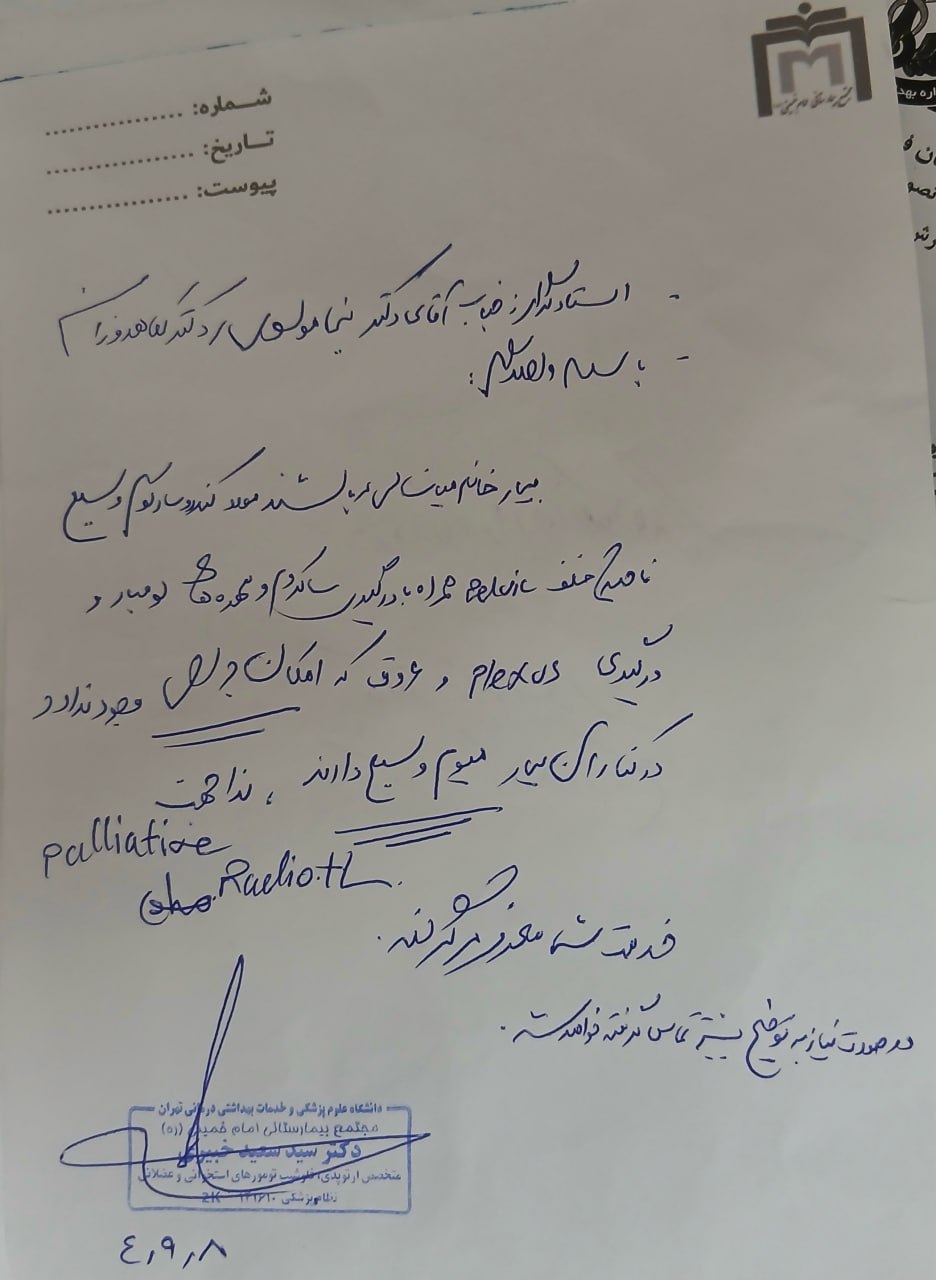

(تصویر مربوط به این مراجعه نیست) Other:

(تصویر مربوط به این مراجعه نیست) Other:

(تصویر مربوط به این مراجعه نیست) Other:

(تصویر مربوط به این مراجعه نیست) Other:

(تصویر مربوط به این مراجعه نیست) Other:

(تصویر مربوط به این مراجعه نیست) Other:

(تصویر مربوط به این مراجعه نیست) Other:

(تصویر مربوط به این مراجعه نیست) Other:

(تصویر مربوط به این مراجعه نیست) Other:

(تصویر مربوط به این مراجعه نیست) Other:

(تصویر مربوط به این مراجعه نیست) Other:

(تصویر مربوط به این مراجعه نیست) Other:

(تصویر مربوط به این مراجعه نیست) Other:

(تصویر مربوط به این مراجعه نیست) Other:

(تصویر مربوط به این مراجعه نیست) Other:

(تصویر مربوط به این مراجعه نیست) Other:

(تصویر مربوط به این مراجعه نیست) Other:

(تصویر مربوط به این مراجعه نیست) Other:

(تصویر مربوط به این مراجعه نیست) Other:

(تصویر مربوط به این مراجعه نیست) Other:

(تصویر مربوط به این مراجعه نیست) Other:

(تصویر مربوط به این مراجعه نیست) Other:

(تصویر مربوط به این مراجعه نیست) Other:

(تصویر مربوط به این مراجعه نیست) Other:

(تصویر مربوط به این مراجعه نیست) Other:

(تصویر مربوط به این مراجعه نیست) Other:

(تصویر مربوط به این مراجعه نیست) Other:

(تصویر مربوط به این مراجعه نیست) Other:

(تصویر مربوط به این مراجعه نیست) Other:

(تصویر مربوط به این مراجعه نیست) Other:

(تصویر مربوط به این مراجعه نیست) Other:

(تصویر مربوط به این مراجعه نیست) Other:

(تصویر مربوط به این مراجعه نیست) Other:

(تصویر مربوط به این مراجعه نیست) Other:

(تصویر مربوط به این مراجعه نیست) Other:

(تصویر مربوط به این مراجعه نیست) Other:

(تصویر مربوط به این مراجعه نیست) Other:

(تصویر مربوط به این مراجعه نیست) Other:

(تصویر مربوط به این مراجعه نیست) Other:

(تصویر مربوط به این مراجعه نیست) Other:

(تصویر مربوط به این مراجعه نیست) Other:

(تصویر مربوط به این مراجعه نیست) Other:

(تصویر مربوط به این مراجعه نیست) Other:

(تصویر مربوط به این مراجعه نیست) Other:

(تصویر مربوط به این مراجعه نیست) Other:

(تصویر مربوط به این مراجعه نیست) Other:

(تصویر مربوط به این مراجعه نیست) Other: